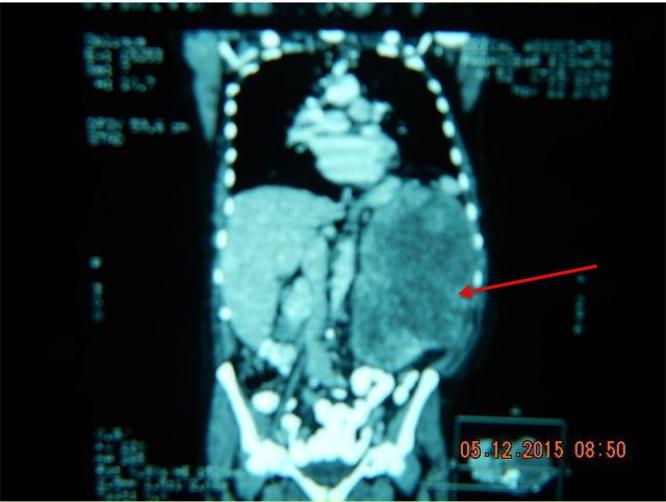

A 52year old male presented with a one year history of progressive weight loss, a gradually enlarging abdomen and no other admissible symptom, including no haematuria. The mass started on his left side of the abdomen. CT scans showed a large tumour arising from the left kidney.

A combined Urological and vascular approach was chosen in view of the CT scans images of huge renal veins and collateral vessels. The left pleural cavity was elevated by the mass pushing on the left diaphragm and the heart was also displaced cranially as the mass made its own space. Bowels were displaced as the giant mass reached into his pelvis. A thoraco abdominal supra12 rib bed approach was adopted. The rib was not resected nor was the pleural cavity opened. Histological diagnosis was renal leiomyosarcoma.

一名52岁男性,有一年逐渐体重减轻、腹部逐渐增大的病史,无其他可接受的症状,包括无血尿。肿块起始于他的腹部左侧。CT扫描显示左肾有一个大肿瘤。

鉴于CT扫描显示巨大肾静脉和侧支血管的图像,选择了泌尿外科和血管外科联合的方法。肿块推挤左膈肌使左胸腔抬高,随着肿块占据自身空间,心脏也向上移位。当巨大肿块延伸至盆腔时,肠道也被移位。采用了经第12肋床的胸腹联合入路。肋骨未切除,胸腔也未打开。组织学诊断为肾平滑肌肉瘤。